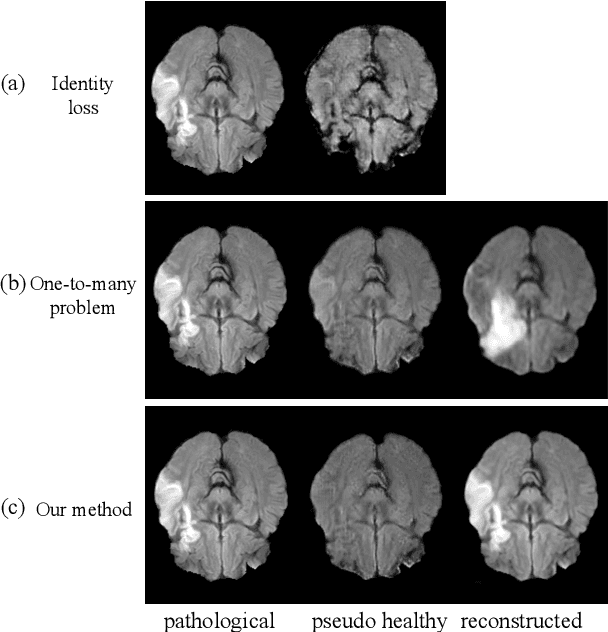

Abstract:Pseudo-healthy synthesis is the task of creating a subject-specific `healthy' image from a pathological one. Such images can be helpful in tasks such as anomaly detection and understanding changes induced by pathology and disease. In this paper, we present a model that is encouraged to disentangle the information of pathology from what seems to be healthy. We disentangle what appears to be healthy and where disease is as a segmentation map, which are then recombined by a network to reconstruct the input disease image. We train our models adversarially using either paired or unpaired settings, where we pair disease images and maps when available. We quantitatively and subjectively, with a human study, evaluate the quality of pseudo-healthy images using several criteria. We show in a series of experiments, performed on ISLES, BraTS and Cam-CAN datasets, that our method is better than several baselines and methods from the literature. We also show that due to better training processes we could recover deformations, on surrounding tissue, caused by disease. Our implementation is publicly available at \url{https://tobeprovided.upon.acceptance}